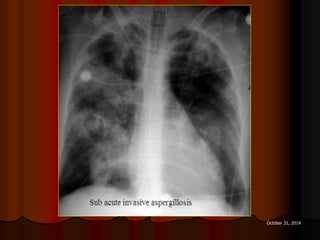

ASPERGILLOME

DẤU HIỆU LỤC LẠC

 Sign of tintinnabulum = Signe de grelot.

 Nấm Aspergillus có thể gây bệnh ở người với 2 thể chính:

 Thể xâm lấn mạch máu (Angioinvasive Aspergillosis): tổn

thương lan toả, gặp ở người có cơ địa suy giảm miễn dịch. Ở

thể này ta có dấu hiệu vầng hào quang (halo sign) trên CT.

 Thể banh nấm (Saprophytic Aspergillosis = Aspergilloma):

hình thành banh nấm (fungus ball) trong lòng các tổn thương

hang ở phổi, thường gặp ở BN có hang lao. Thể này cho dấu

hiệu lục lạc (Tintinnabulum sign) hay dấu hiệu liềm khí (Air

crescent sign) tuỳ theo tác giả.